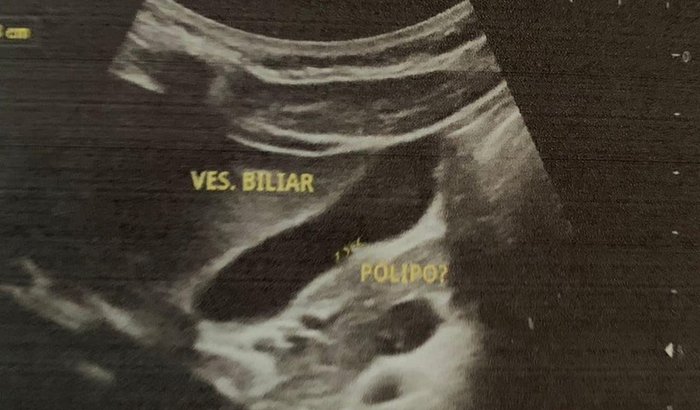

Boa noite , estou passando aqui pra pedir uma ajudinha de cada um , que Deus tocar no coração de estar ajudando , minhas filhas estar precisando de cirurgia urgente , pra poder tirar a vesícula a Geiza precisa tirar a vesícula, porque estar com muita pedra , e faz 5 meses vomitando direto , nada para no estômago dela , vai tirar a vesícula, e a outra minha filha Joice , estar com dignostico de um tumor na vesícula , que é pólipo e precisa tirar também , peço que vocês poder ajudar com o que sentir no coração já agradeço muito , aqui é um coração de uma mãe lutando pela vida das minha filhas , precisa tirar o tumor logo , porque vira o maligno, e vira o câncer , passou hoje com cirurgião, ele avaliou que é só tirando a vesícula , só que é caro demais não tenho o dinheiro , as duas cirurgia e 16 mil , 7,600 só do cirurgião, mais 1,000 da santa casa. Elas precisa da cirurgia , porque uma não come mais , porque a pedra tampo a vesícula , e a outra Tumor estar crescendo , que Deus abençoe cada um que poder ajudar até com 0,50 Deus abençoe grandemente a vida de vocês , quem não poder , ajuda colocar nas oração , obrigada pela atenção , vou estar postando as fotos dos exames delas …🥹❤️ o Que vocês sentir de ajudar , Deus vai retribuir todos , pra fazer pelo sus mesmo que é urgente demora muito